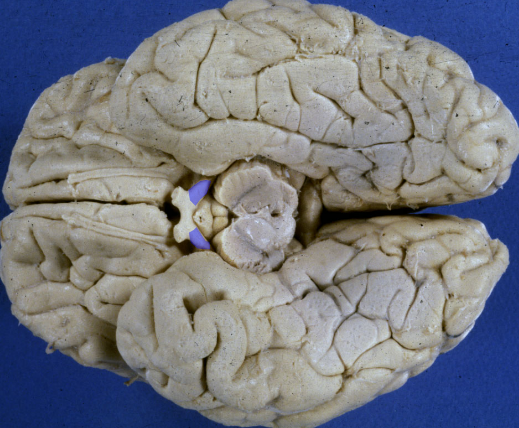

optic tract

thalamus and the crus cerebri

A lesion of the right optic tract causes a complete loss of vision in the left hemifield:

contralateral “homonymous” hemianopsia.

lateral geniculate n.

input is from the?